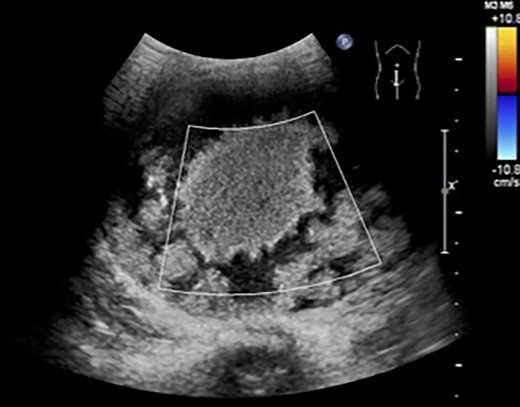

The patient was a 10-year-old girl. She visited our hospital after her grandmother noticed a mass in her lower abdomen that she had been aware of for 6 months. Abdominal ultrasonography revealed that she had a large mass centered in her lower abdomen. The tumor border was clear, the internal structure was heterogeneous and the blood flow was poor (Fig. 1). We suspected an ovarian tumor, but blood tests showed no elevated tumor markers such as AFP and CA19–9. Abdominal magnetic resonance imaging revealed a cystic mass 10 cm in diameter with high intensity on T1-weighted images and high intensity on T2-weighted images (Fig. 2). Abdominal computed tomography revealed a spleen near the navel and a cystic lesion with poor contrast that continued from the lower pole of the spleen (Fig. 3).

Abdominal magnetic resonance imaging revealed a cystic mass 10 cm in diameter with high intensity on T1-weighted images (upper) and high intensity on T2-weighted images (lower).